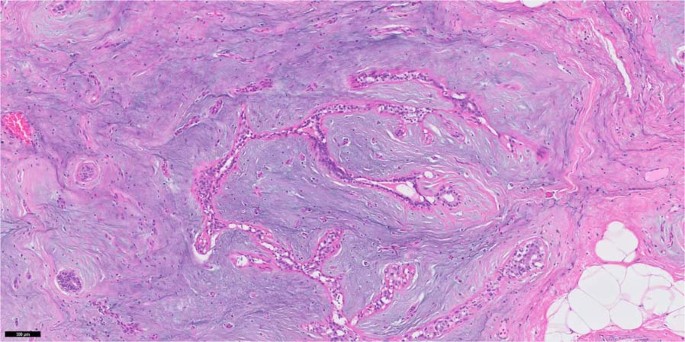

Stroma predominant phyllodes tumour, often in the setting of borderline grade, may resemble fibromatosis (Fig. 18). Finding stromal fronds on histology allows the correct diagnosis. Presence of periductal stromal condensation and narrow elongated clefted ducts should raise suspicion of a phyllodes tumour. Immunohistochemistry for CD34 generally shows stromal positivity in phyllodes tumours, with a higher rate in the benign grade [62,63,64], whereas it is negative in fibromatosis [65, 66]. Nuclear beta-catenin, often described as a diagnostic feature for fibromatosis, is also observed in phyllodes tumours, so it cannot be used for discriminating these two lesions [65, 67,68,69]. Fibromatosis-like metaplastic carcinoma (Fig. 19) is positive for epithelial markers on immunohistochemistry—nuclear beta-catenin can also be expressed [67, 70].